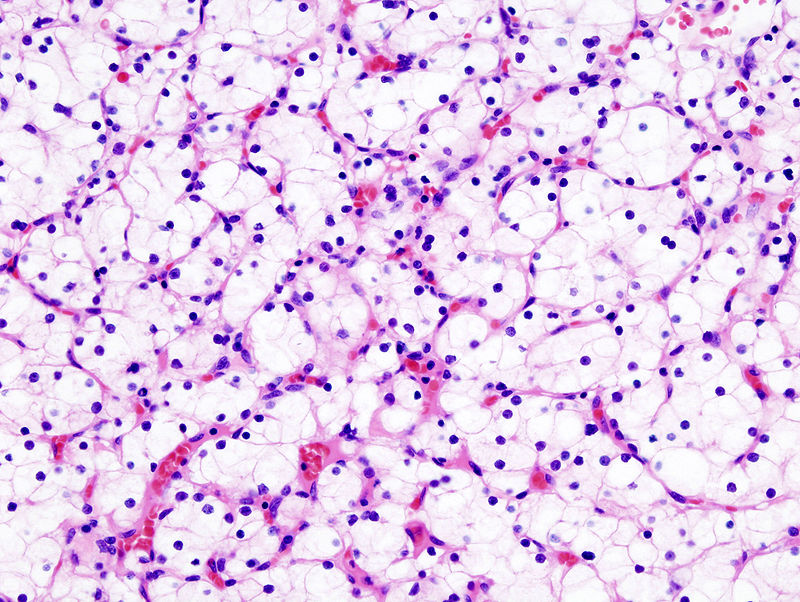

When examined under a microscope, the most common variant of renal cell carcinoma shows clear cytoplasm or a clear cell type.

Loss of the tumor suppressor gene VHL causes an increase in the growth-promoting hormone IGF-1 and the transcription factor HIF, which in turn causes an increase in the growth hormones VEGF and PDGF.